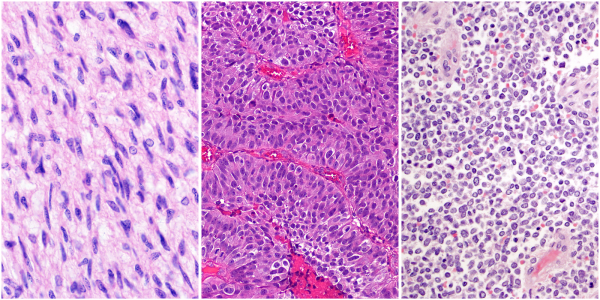

圖1:STAG2是(從左至右)膠質(zhì)母細胞瘤、膀胱癌和骨癌尤文氏肉瘤中常見的突變基因之一。